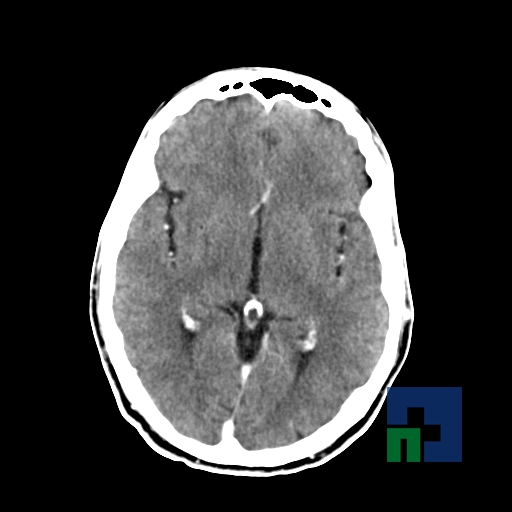

Examinare de rutină cerebrală, nativ și cu substanță de contrast (SDC) pentru diagnosticul:

- Accidentelor vasculare cerebrale ischemice sau hemoragice

În cazul traumatismelor cranio-cerebrale:

- Evaluarea deplasării liniei mediane

- Evaluarea cisternelor perimezencefalice

- Diagnosticul edemului cerebral, a contuziei cerebrale, a leziunilor axonale difuze edematoase/hemoragice, a dilacerării cerebrale, a hematomului intraparenchimatos posttraumatic, a hematoamelor subdurale/extradurale (acute, subacute, cronice), a hemoragiei intraventriculare, a hemoragiei subarahnoidiene

- Diagnosticul traumatismelor de bază de craniu

- Diagnosticul fistulei LCR

- Diagnosticul herniilor cerebrale

- Diagnosticul fracturilor: